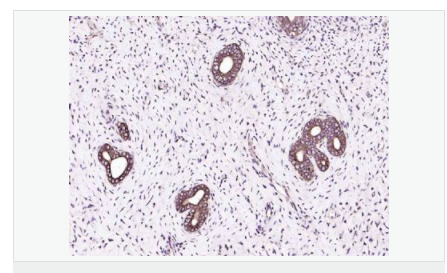

產(chǎn)品應(yīng)用WB=1:500-2000 ELISA=1:5000-10000 IP=1:20-100 IHC-P=1:100-500 IHC-F=1:100-500 IF=1:100-500 (石蠟切片需做抗原修復(fù))

image.png